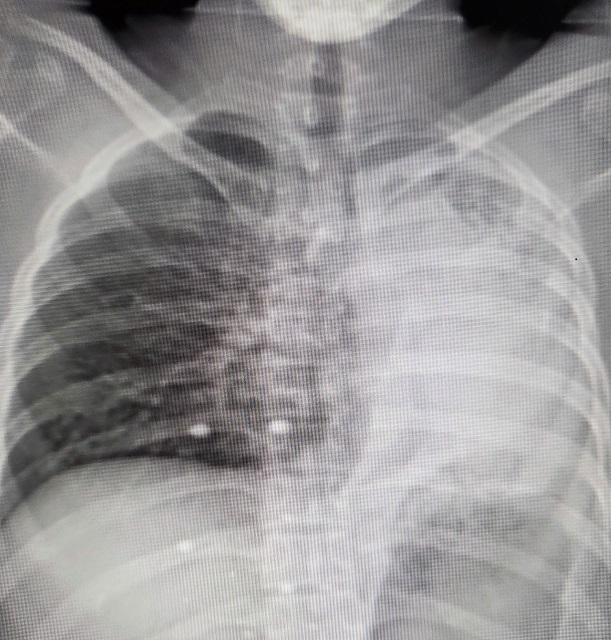

28/03/2025 13:02Người đàn ông Hà Nội có lá phổi xẹp, đặc như tấm bìa cứng

Cách đây 1 năm, anh Nguyễn Văn B (sống tại Hà Nội) được chẩn đoán mắc lao phổi. Mặc dù anh B đã duy trì điều trị tích cực nhưng đến tháng 3/2025, phổi trái của anh xẹp hoàn toàn do phế quản gốc bị hẹp tắc.

Anh B được chuyển đến Khoa Phẫu thuật Lồng ngực, Bệnh viện Bạch Mai. Kết quả thăm khám lâm sàng và chụp chiếu cho thấy anh B đối diện với nguy cơ mất một lá phổi vĩnh viễn. Phế quản gốc trái chỉ còn khe hẹp 2mm, phổi xẹp, đặc như tấm bìa cứng. Nếu anh B không phẫu thuật trong 2 tuần, phổi sẽ hoại tử.

Sau khi thảo luận và lập “chiến lược” phẫu thuật, điều trị hồi phục sau mổ, các bác sĩ đã quyết định tiến hành ca phẫu thuật. Sau 4 giờ tập trung cao độ, ê-kíp phẫu thuật đã cắt bỏ thành công đoạn phế quản hẹp 3cm và khâu nối tái tạo đường thở. Chỉ 24 giờ sau mổ, phổi trái của anh B đã giãn nở trở lại.